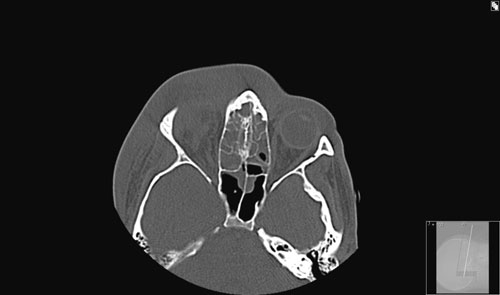

Øre-nese-hals-lege hadde tilsyn fire dager etter innkomst. Han fant økende periorbitalt ødem. Fremre og bakre rhinoskopi viste ikke påfallende sekresjon i nesekaviteten. Det ble funnet oppvekst av betahemolytiske streptokokker som var sensible for penicillin, og gramnegative staver som var sensible for metronidazol i blodkultur. To dager etter oppstart av behandling hadde CRP falt fra 200 til 100, men fire dager etter innkomst var CRP økt til 155. Det ble tatt CT av bihuler uten kontrast som viste pansinusitt og orbital hevelse som presset bulbus oculi utover (fig 1).